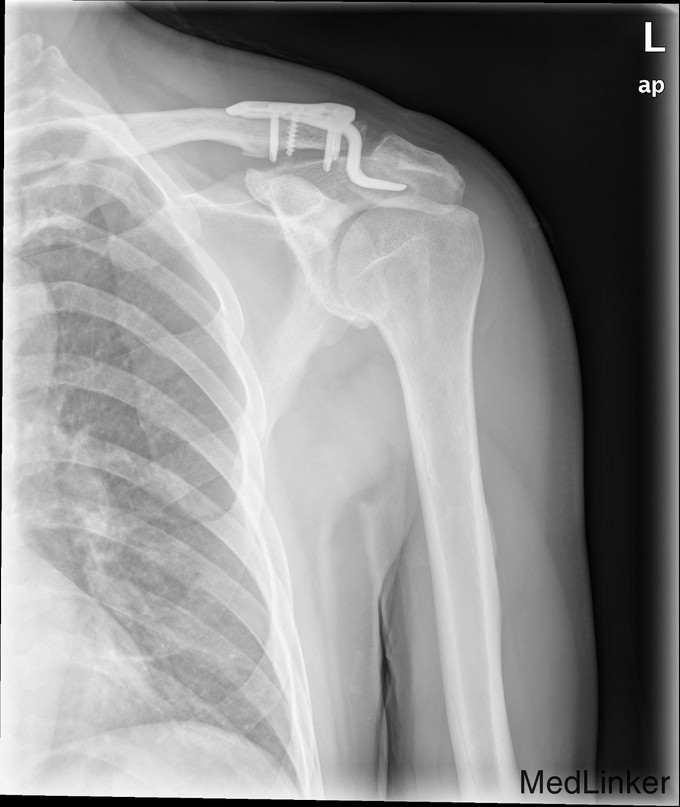

完善术前检查和准备后,行左肩锁关节脱位切开复位内固定术,术顺,术后安返病房,内固定使用锁骨钩。

随访示内固定在位,复位位置可。